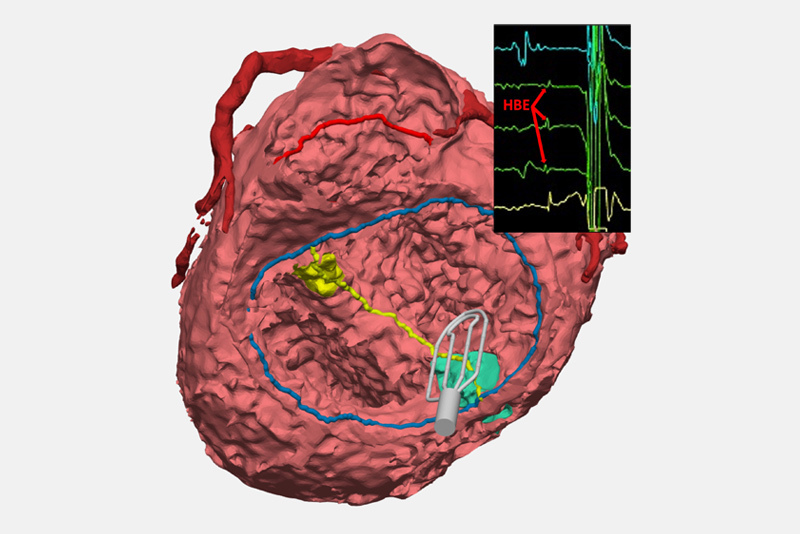

One such recent advancement is already reducing heart block. Our team has developed a protocol for using an electrophysiology (EP) catheter that collects electrical signals from the electrical conduction system of open, beating hearts during surgery. The electrophysiologist in the operating room interprets these signals and communicates the location of conduction tissue back to the surgeons, who then mark the spot of the tissue to avoid inadvertent injury while operating.

EP mapping also allows us to record the location of conduction tissue for further study. We’re finding that anatomical variables — like how a patient’s ventricles are arranged, where the heart is located inside the chest, and how the atria are oriented — can influence the location of the conduction system. While some of these findings were first discovered in older anatomy studies, our rapidly growing conduction mapping experience is enabling us to better understand where the conduction system is located across all variants of complex CHD.

Our program is also creating 3-D models of the cardiac anatomies of every CHD patient who benefits from EP mapping in surgery. Ultimately, those individual models will be available in a digital library that will let clinicians review the influences that different anatomies have on conduction, which may help cardiologists and surgeons developed surgical plans informed by the conduction’s system location for each particular type of CHD.